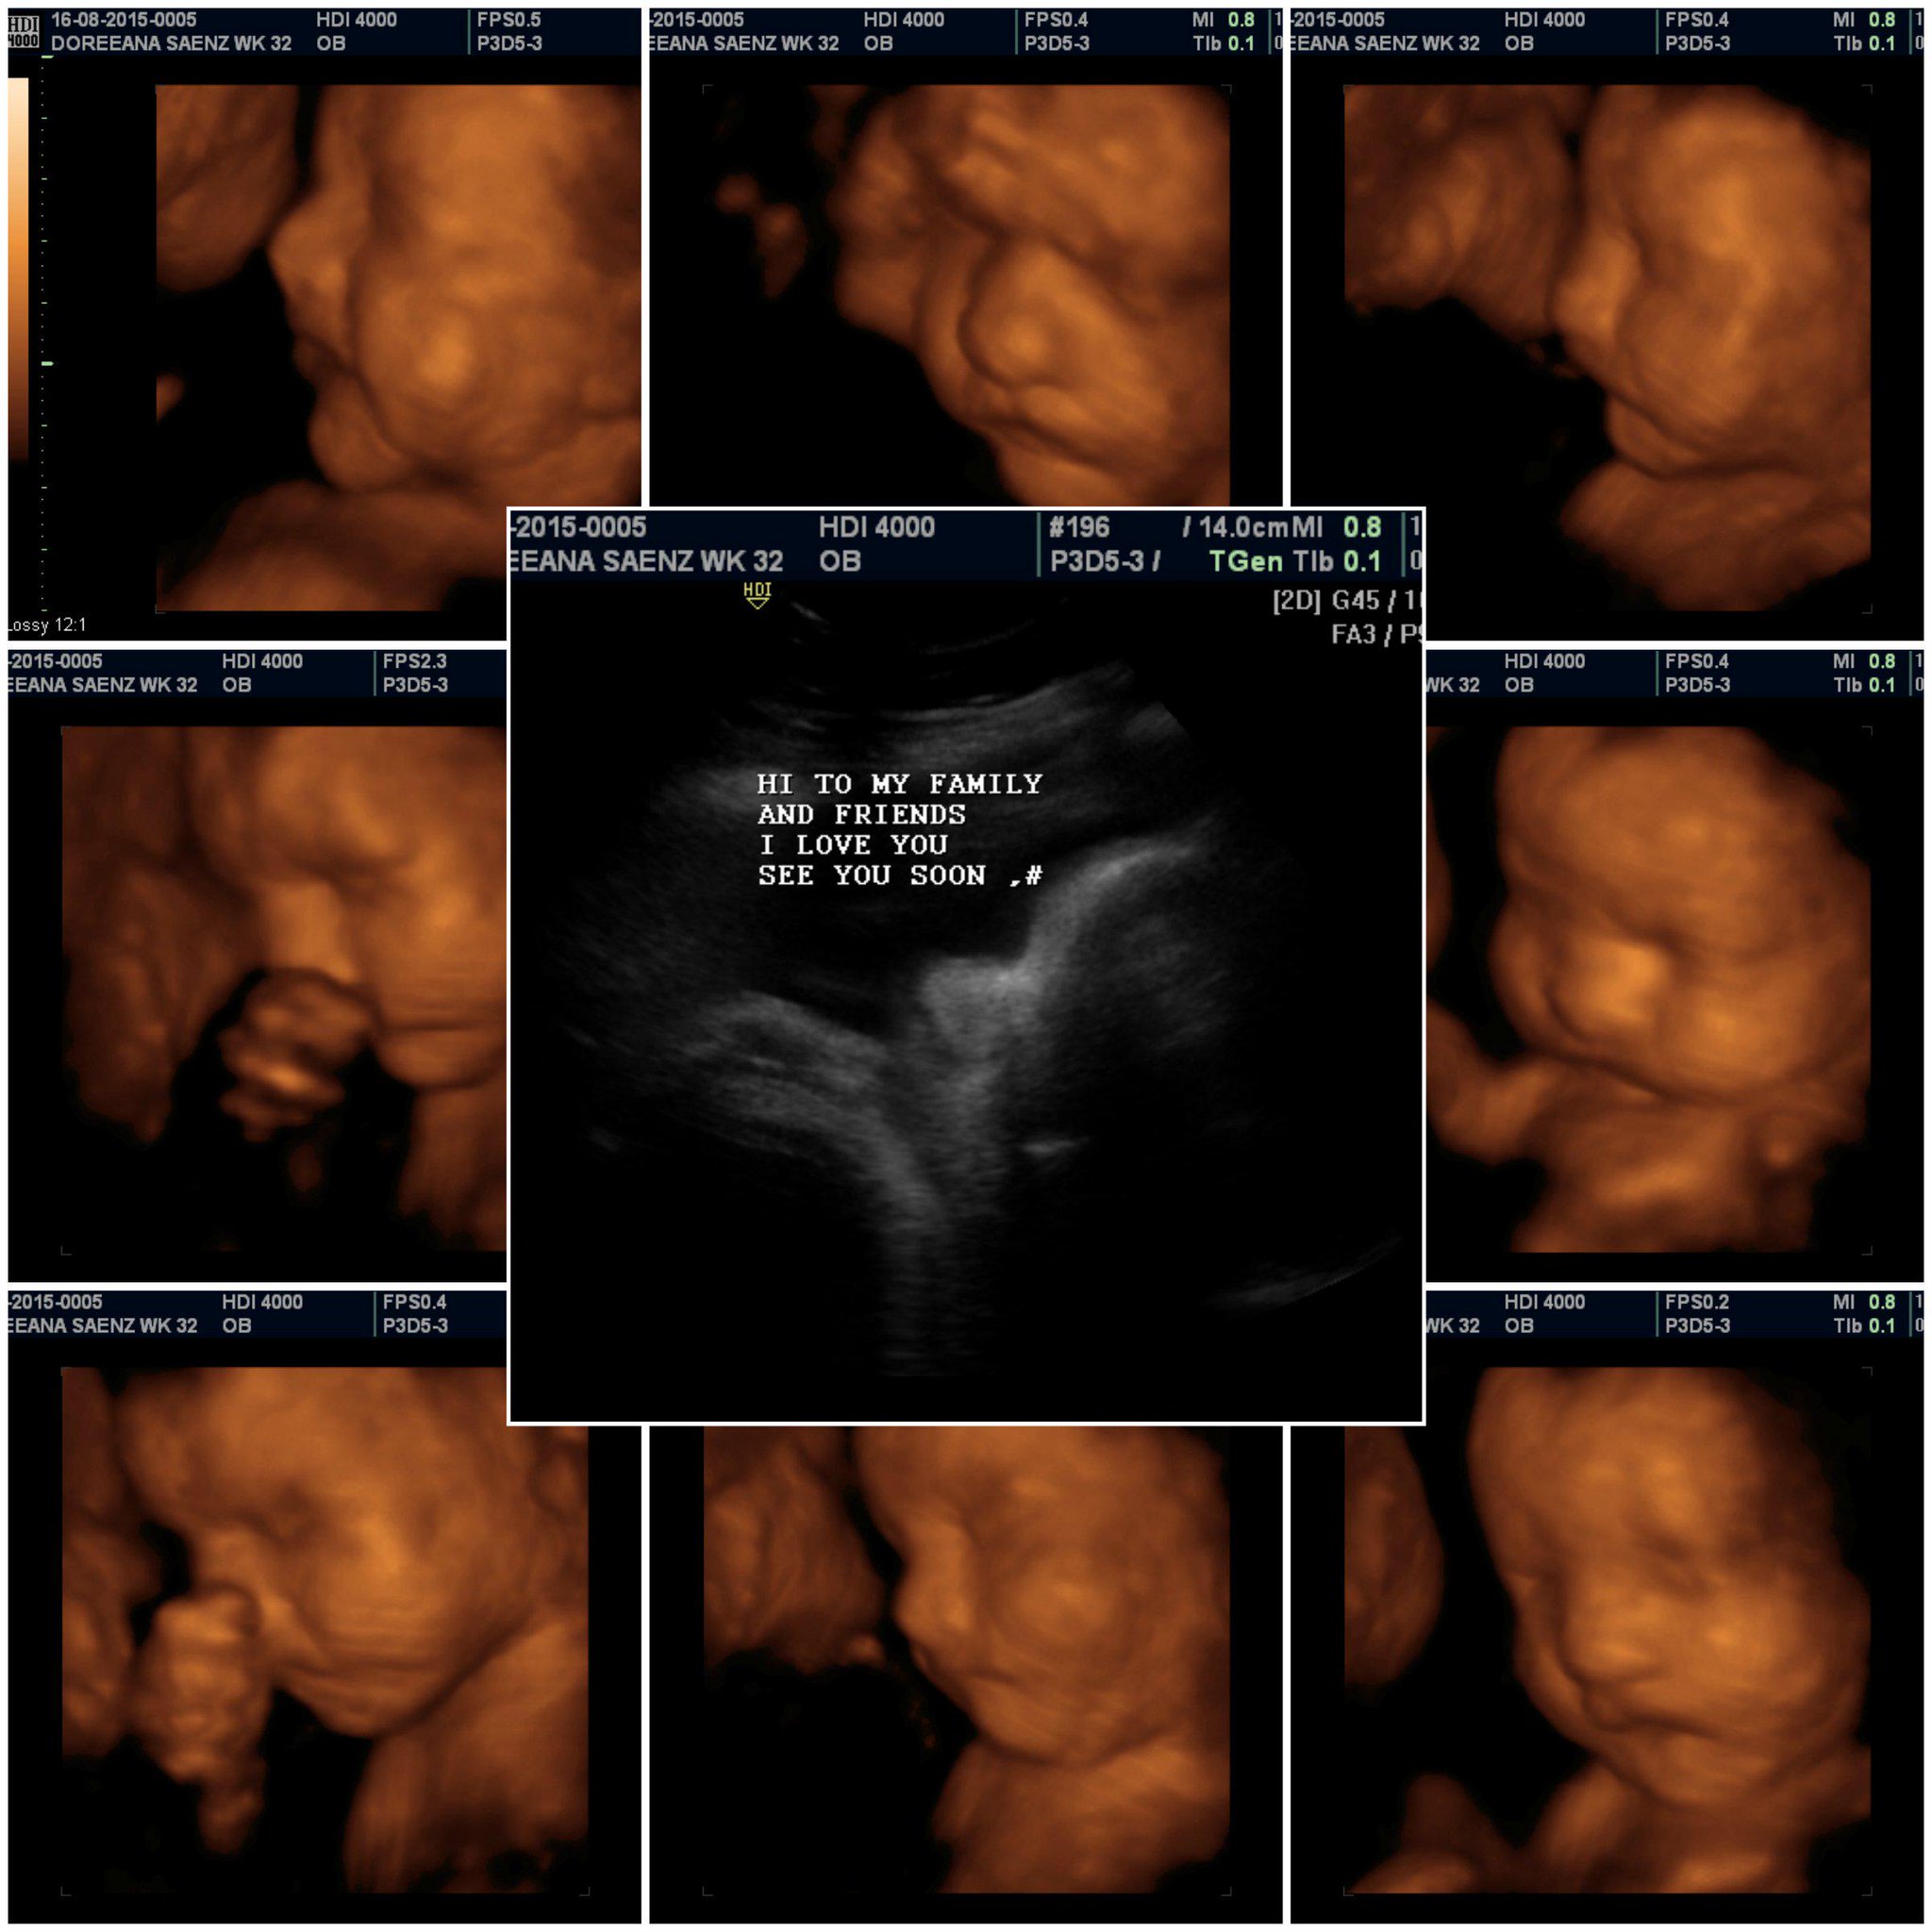

3D Baby Ultrasound on Twitter: “Thank you Doreena and Family http://t …